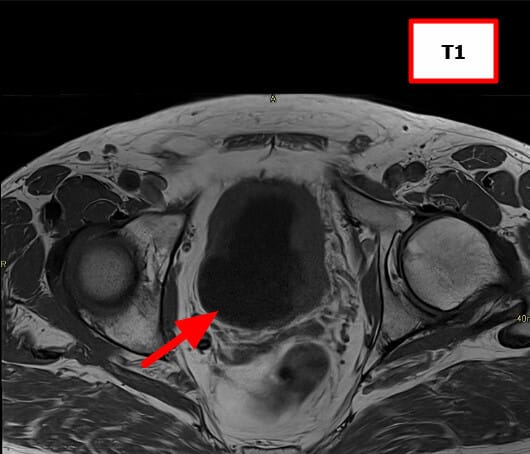

방광암 (Bladder Cancer)

[임상양상]

– 가장 특징적인 증상은 무통성 육안적 혈뇨입니다.

– 빈뇨, 배뇨통, 잔뇨감 같은 자극 증상이 동반될 수 있습니다.

– 진행 시 골반통, 수신증(요관 폐쇄), 체중 감소 등 전신 증상이 나타날 수 있습니다.

[진단]

– 소변검사: 혈뇨 확인.

– 소변세포검사: 암세포 확인 가능.

– 방광경검사(Cystoscopy): 진단의 gold standard, 직접 종양 확인 및 조직생검 가능.

– 영상검사(CT urography, MRI): 종양의 범위 및 전이 평가.

– 병리검사: 요로상피암(urothelial carcinoma), 편평상피암, 선암 등 조직학적 아형 구분.

MRI (Magnetic Resonance Imaging)

연부조직 대비가 뛰어나 방광 침윤 깊이를 정밀하게 파악